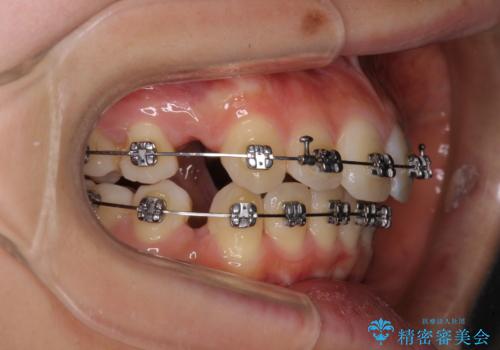

- メタルブラケット

- 1年5ヶ月

- 10-30回

上下左右4本抜歯する場合には、通常2年から2年半ほどの期間を要しますが、僅か1年半で終了することができました。